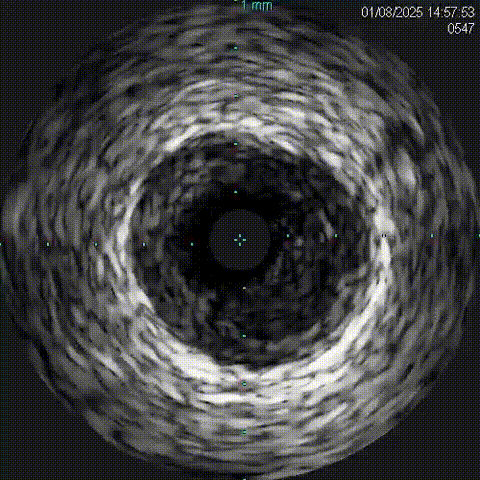

右冠血管内超声影像(IVUS)

对侧造影证实GW3位于远端真腔,跟进微导管,撤出GW3送入GW1,先后送入balloon 1(1.5x1.5mmEmerge)、Ballon 2(2.0x15mmGusta)、Ballon3 (2.0x15mm 心迅)、Ballon 4(2.5x15mm cutting)、Ballon5(2.5x15mm NC Sprinter)、Ballon 6(3.0x15mm NC Sprinter)至RCA病变处预处理后,送入IVUS查看病变性质、程度及血管直径。